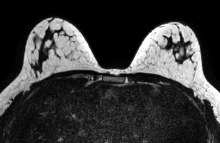

Magnetic resonance imaging (MRI) scans show repetitive blows to the head result in brain changes among youth football players, according to a new study. Study results were presented at the 2018 annual meeting of the Radiological Society of North America (RSNA), Nov. 25-30 in Chicago.